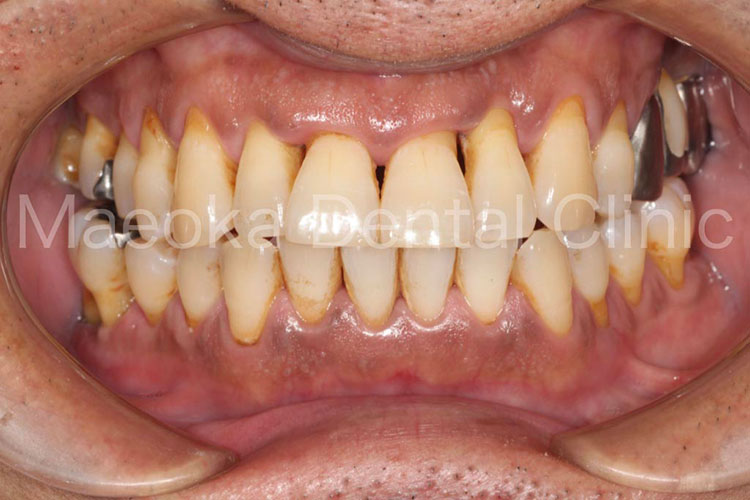

患者さんは49歳女性の方で、「全体的にしっかりと治したい」という主訴で来院されました。

出産を機にお口の環境が悪くなっていったとのことでしたが、勇気が出せずになかなか歯科を受診できなかったそうです。

診査を行うと奥歯の噛み合わせが失われており、審美面、機能面ともに大掛かりな介入が必要な状態でした。

はじめに患者さんから伺った情報を基に、現在の環境になってしまった根本的な原因を模索し、原因除去を行っていきました。その後、歯の移植(右下5を右上3に移植)、部分的な矯正などを行った上で審美的な範囲はセラミックスを用いた被せ物、歯の削除量を最小限にするために見えない箇所は金属を用いた被せ物で最終的な修復を行いました(一部表面的な虫歯は残っていますが、患者さんと相談した上で、今の段階で積極的に削ることは避け、経過観察を行うこととしています)。

プロビジョナルレストレーション(精密な仮歯)を入れた上で機能上問題ないことを確認するなどチェック期間にも時間を要したため、5年に及ぶ治療期間を要しましたが、残りの患者さんの人生の長さを考えると必要十分な治療であったと考えます。

保存不可能と思われる歯が多数ある中ではありましたが、結果として抜歯に至った歯は3本のみで、インプラントを用いることなく、患者さん自身の歯でお口の環境を再構築することができました。

今後はメインテナンスで治療終了時の環境を長期的に維持できるように努めていきます。

治療後(正面)

治療前(上顎咬合面)

治療後(上顎咬合面)

治療前(下顎咬合面)

治療後(下顎咬合面)